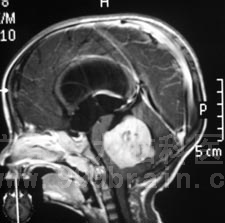

2010年12月1日,小昌在全麻下接受了“右侧脑室腹腔分流术+脑干、四脑室内占位切除术”。术程顺利,术后小昌恢复良好,没有出现抽搐、恶心呕吐等症状,四肢活动良好。术后的病理报告显示:髓母细胞瘤WHO IV级。http://www.999brain.com

术前 术后